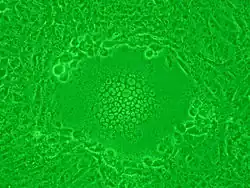

Syncytia can also form when cells are infected with certain types of viruses, notably HSV-1, HIV, MeV, SARS-CoV-2, and pneumoviruses, e.g. respiratory syncytial virus (RSV). These syncytial formations create distinctive cytopathic effects when seen in permissive cells. Because many cells fuse together, syncytia are also known as multinucleated cells, giant cells, or polykaryocytes.[13] During infection, viral fusion proteins used by the virus to enter the cell are transported to the cell surface, where they can cause the host cell membrane to fuse with neighboring cells.